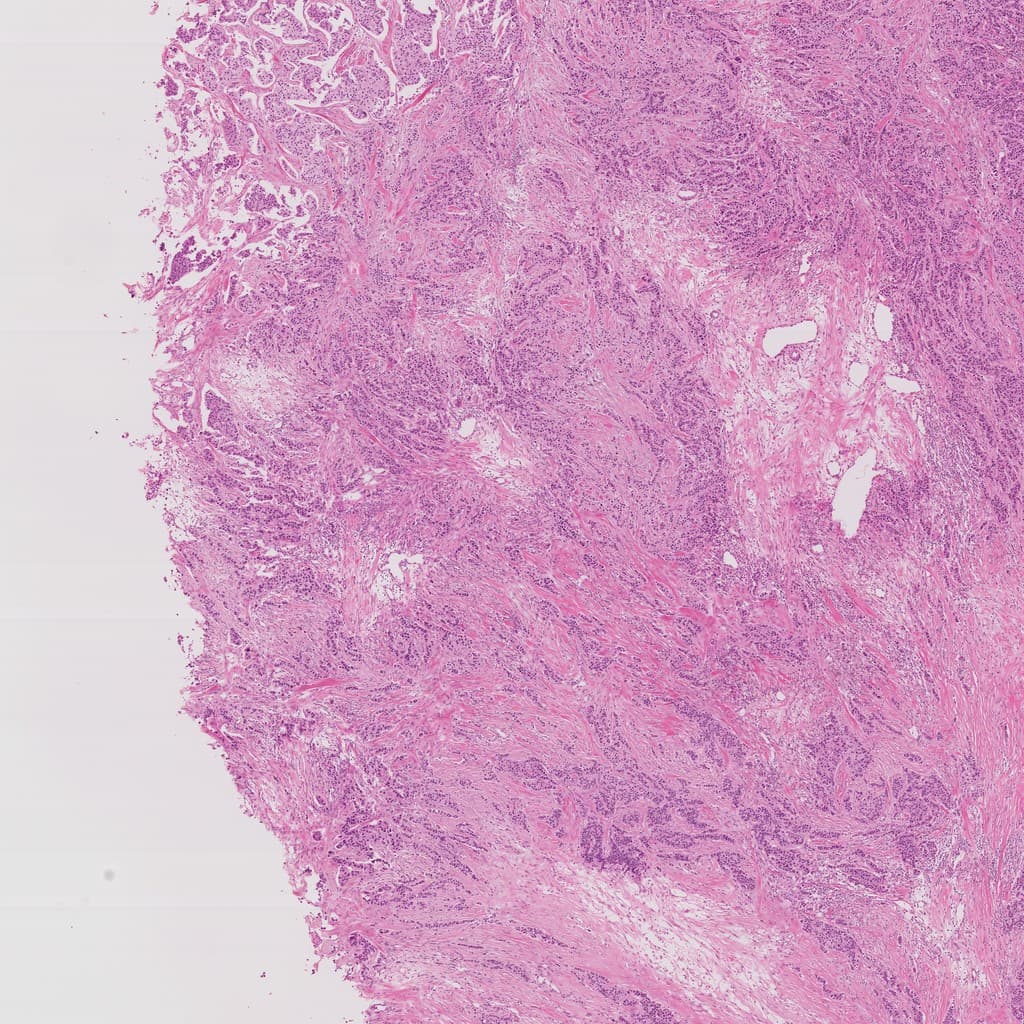

At 10× magnification, dysplastic glands show complex distribution suggesting stromal invasion. Dense cellularity without diffuse necrosis or hemorrhage. Mild stromal inflammatory infiltration, no significant carbon deposition or pseudodense areas from alveolar collapse, excluding non-neoplastic dense shadows.

This region shows loss of normal alveolar structures with acinar and papillary growth patterns, suggesting marginal features of neoplastic proliferation with clear diagnostic value.